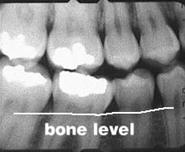

demineralizare osoasa halistereza

resorbtie osoasa

resorbtie osoasa accentuata